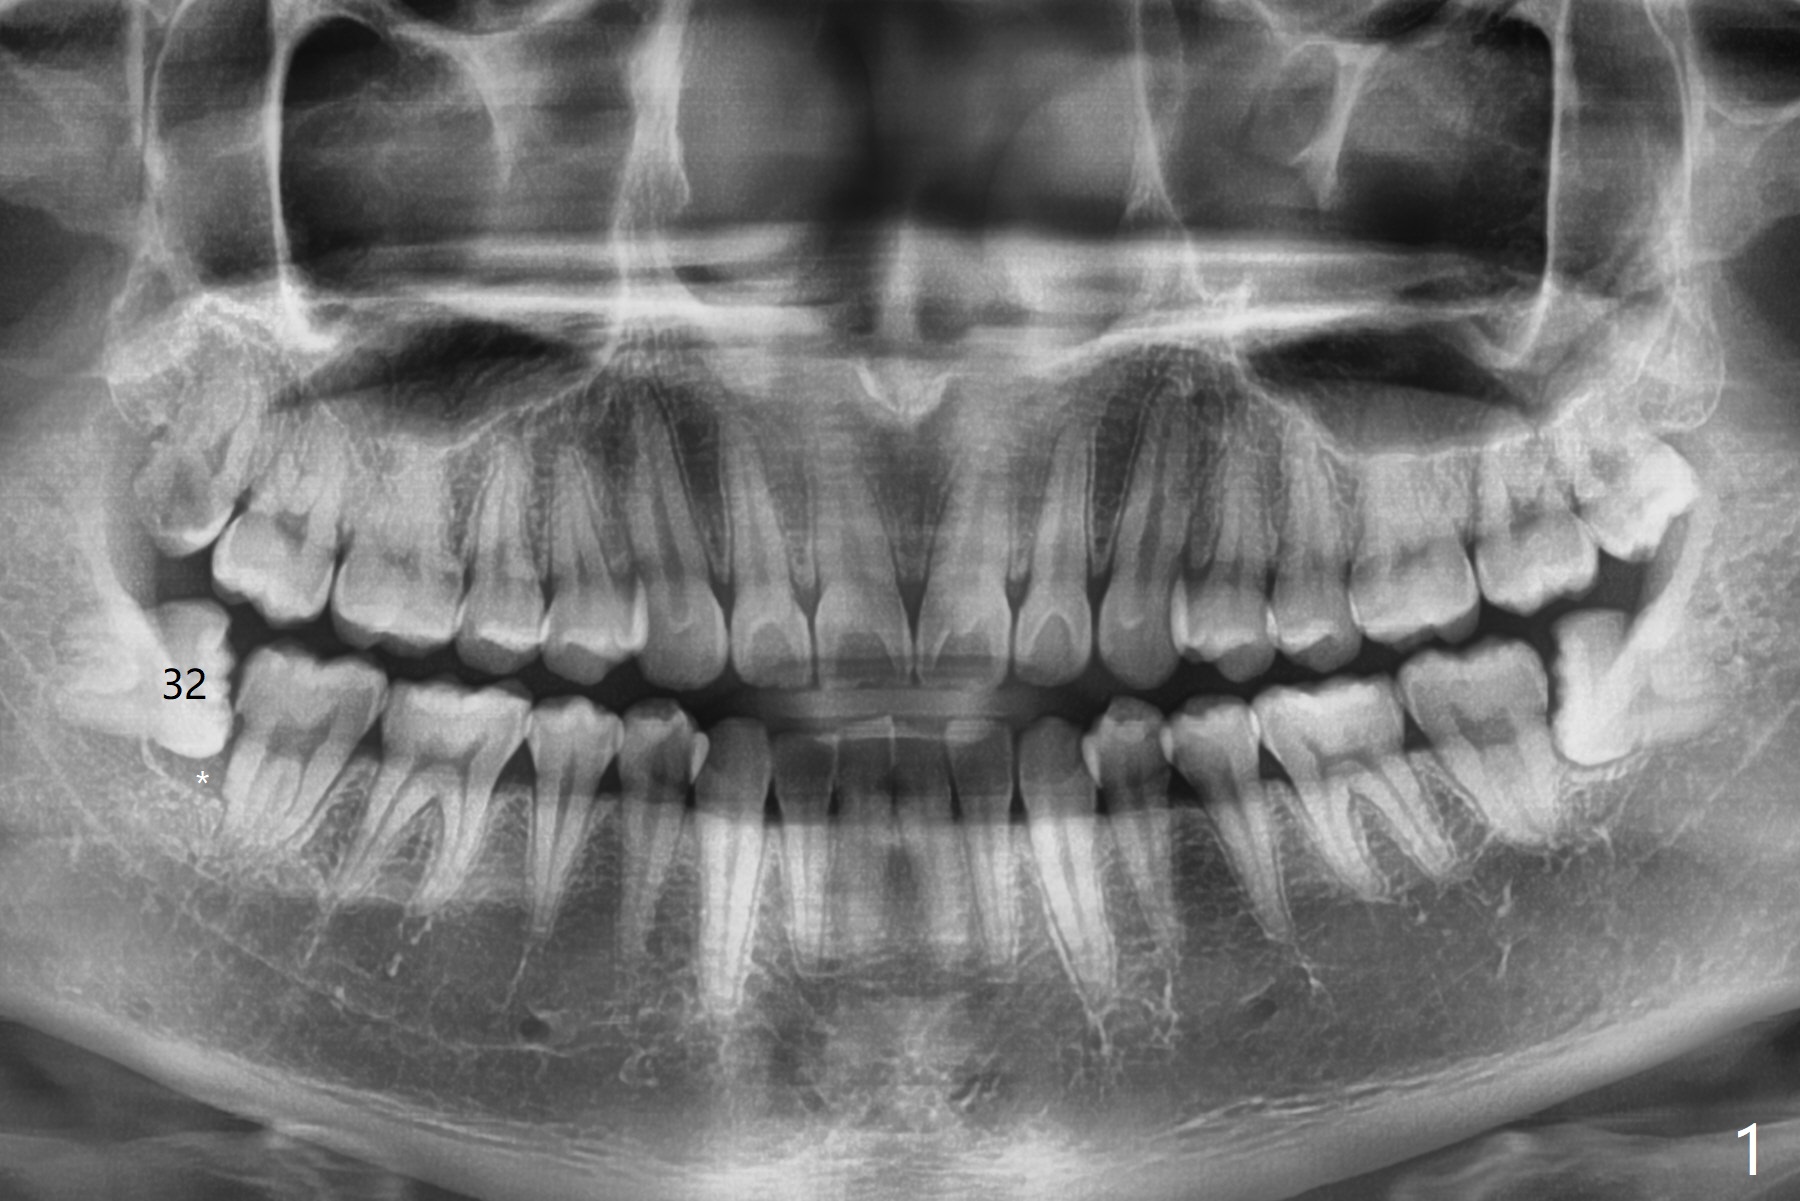

Dental Sac vs. Bone Loss

A 23-year-old man with poor oral hygiene presents to clinic with pain at #1 and 32. Because of bone loss between #31 and 32 (Fig.1 *), Bond Apatite (1 cc, Fig.2 A) is placed in the defect area following insertion of Collagen Plug in the sockets (P, a half). The other half of the Plug is placed coronal to Bond Apatite before suturing with 4-0 PGA.